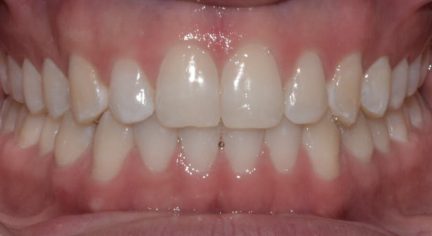

Résultats obtenus

- Relation de classe I maintenue

- Lignes médianes coïncidentes

- Courbe de Spee nivelée

- En raison d'un écart de Bolton, la réduction interproximale était nécessaire dans l'arcade inférieure pour obtenir une relation correcte entre le surplomb et le surplomb. La réduction interproximale établie entre l'incisive centrale supérieure n'a pas été appliqué, de sorte que la fermeture du diastème pouvait avoir un raccord avec les derniers aligners.

État final